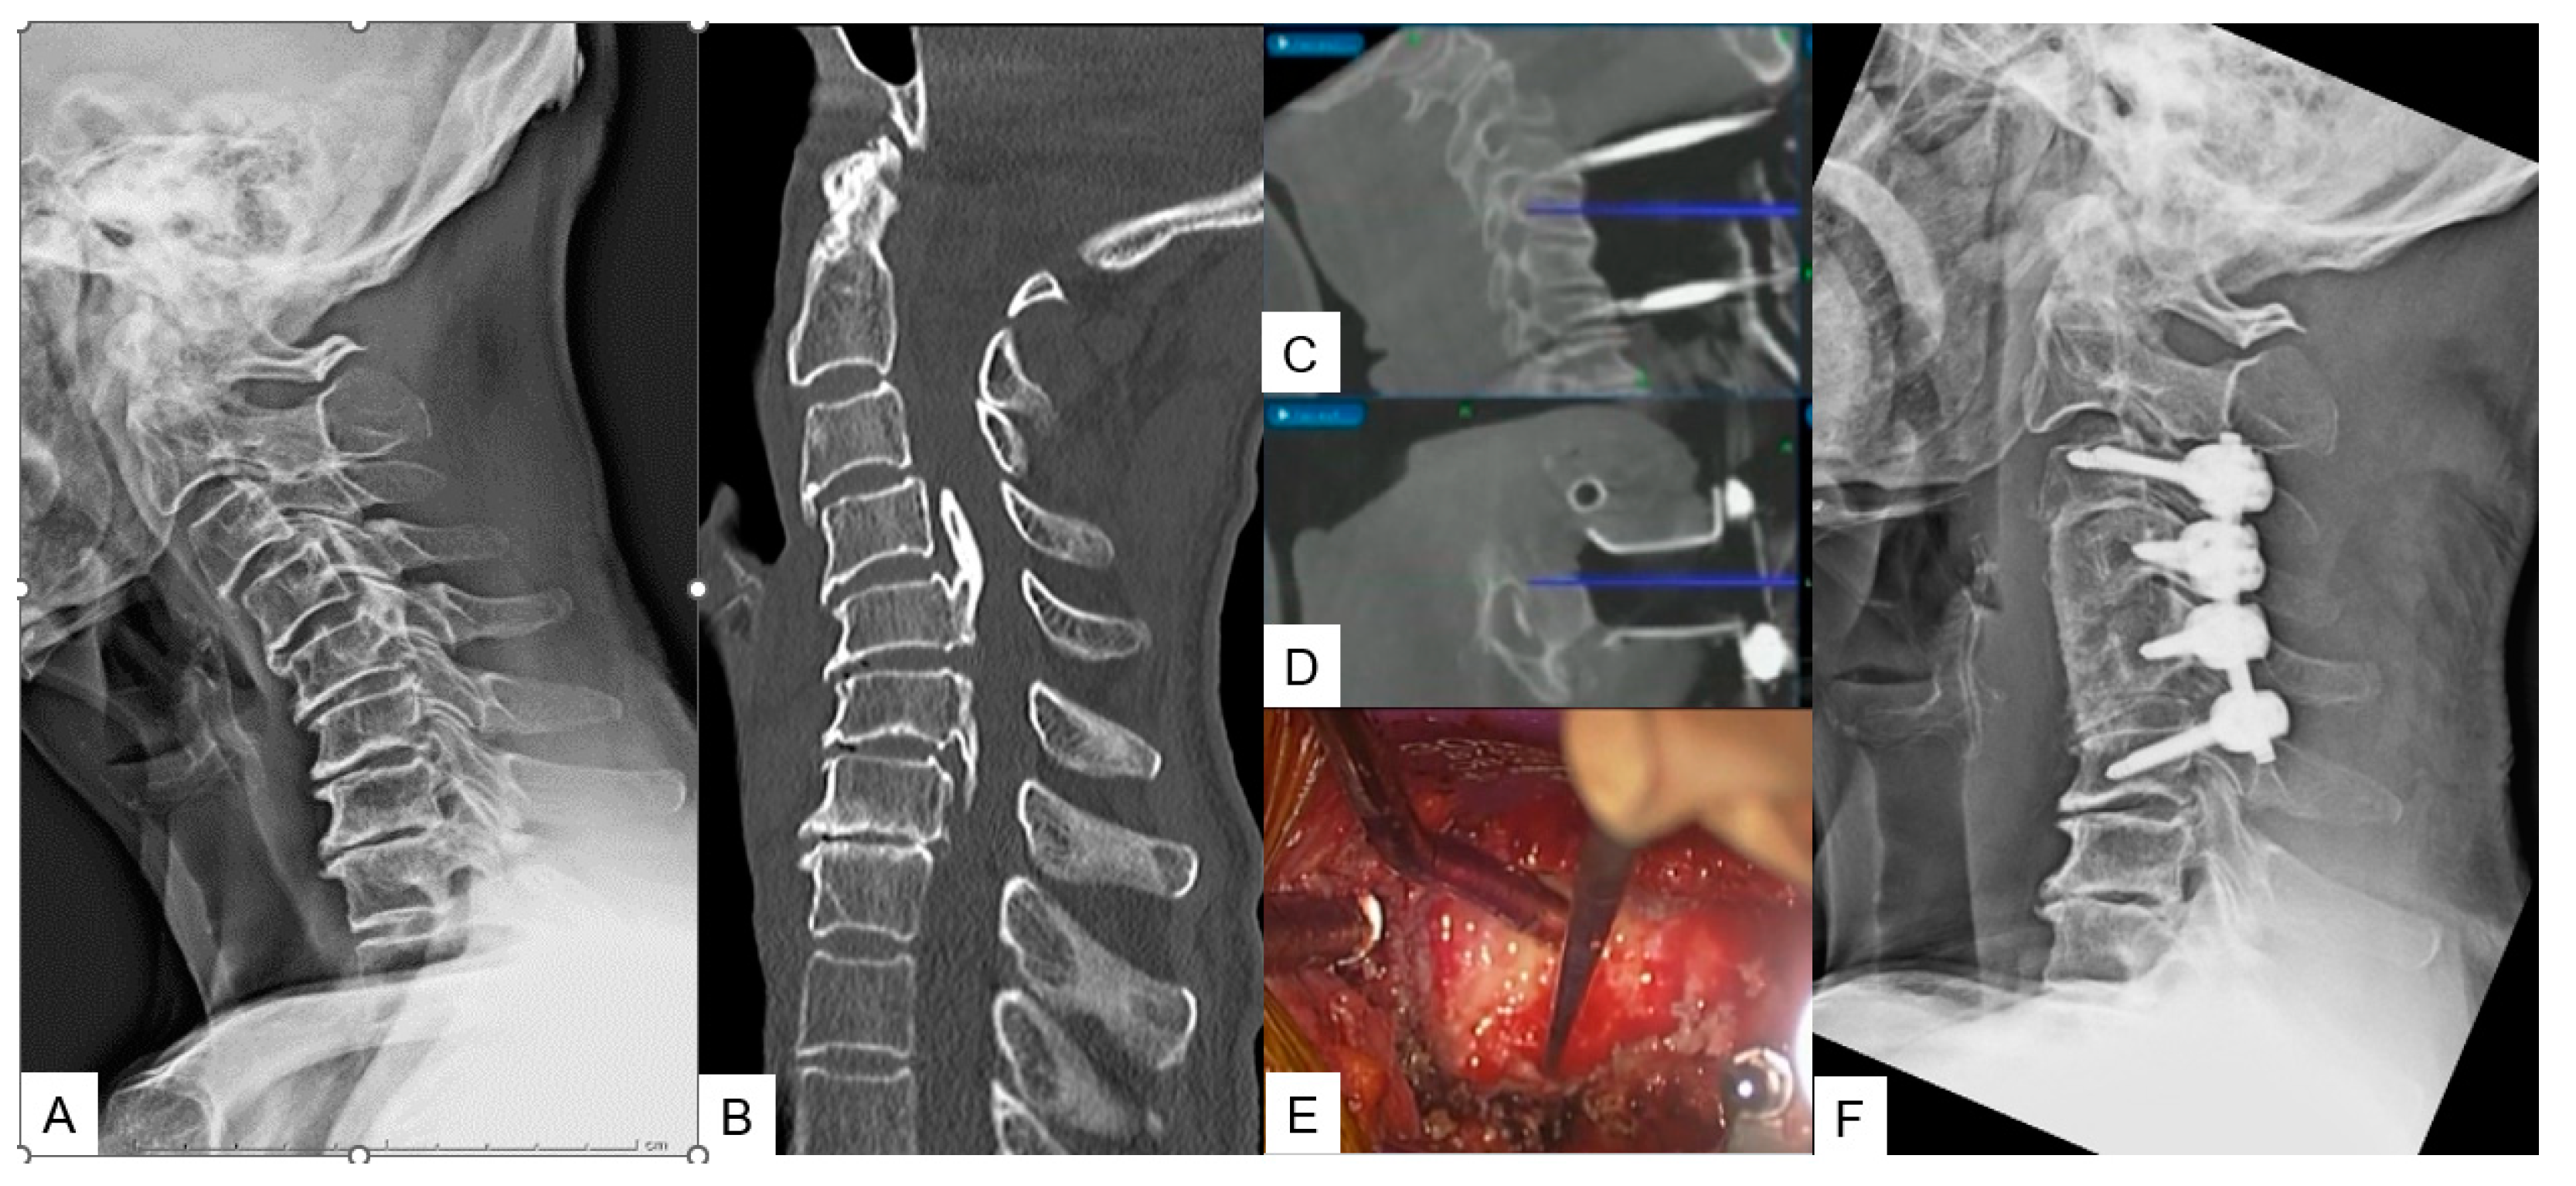

Figure 4. Case 4, 68 years old male, Anterior atlantoaxial subluxation, Modified Goel fixation. A: Preoperative cervical lateral radiogram, B: Preoperative midsagittal T2 weighted MR imaging, C: Intraoperative navigated high-speed burr, D: Intraoperative lateral mass screwing, E: Various C1 lateral mass entry points in lateral, F: Insertion point of mid-point technique (red circle), G: Postoperative cervical lateral radiogram.

2.2.3. Midpoint technique for C1 lateral mass screw (LMS) placement

A careful and precise posterior surgical exposure is required for this technique. Following which, retraction of the posterior atlantoaxial venous plexus inferiorly is necessary by using a Penfield retractor to separate the posterior arch from the inferior aspect. Firstly, the entry point for this screw is 8mm anterior from the posterior arch and caudal aspect (Midpoint). A navigated high-speed burr with a 2mm tip is used for precision and safety. Secondly, by using a navigated pedicle probe, penetration down to the anterior aspect of the cortex of C1 anterior arch must be made. At the end, bicortical placement of C1 LMS is performed.

2.2.2. Modified Goel technique

Stabilization of C1-C2 level can prove to be challenging due to lower fusion rates compared to the other cervical levels, as the motion in this particular segment is significantly higher. For this approach we propose C1 LMS with C2 pedicle screw insertion. A careful posterior approach as described in Midpoint technique should be made to avoid vessel injury. After that the ideal entry point should be marked with a high speed burr without applying strong downward forces at C2 vertebra. Finally, the trajectory is made by using a navigated pedicle probe with appropriate tapping.